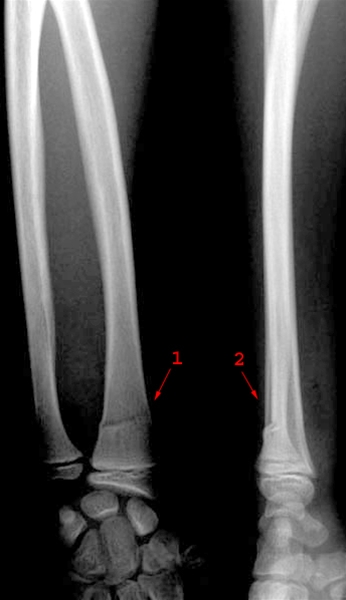

Fraktur distalt i radius

Fraktur distalt i radius med let dorsal vinkling af distale fragment (1 og 2). Bruddet er en såkaldt infraktion, der ligesom "greenstick" frakturen er et inkomplet brud, hvor kun den ene kortikalis er fraktureret.